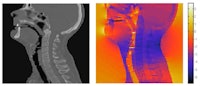

![]() |

| MR images of the phantom before and after correction, the measured field map used for correction, and a CT image. |

To test the validity of this correction procedure, the researchers examined a water-filled phantom containing a regular 2D plastic grid. The phantom was imaged using a GRE sequence with a low gradient strength (0.93 mTm-1), which leads to large image deformations.

"We acquired images with low gradient strength to illustrate the large deformations that may occur and show that we are able to correct the distortions even in those cases," Crijns explained. "This proves the robustness of our implementation."

Crijns and colleagues determined the locations of the central 64 grid points before and after correction, and compared these to their expected locations, as defined from a CT image of the phantom. The average difference between the MRI-obtained grid point locations and their real coordinates was 0.65 mm before correction. After correction, this was reduced to 0.30 mm. The maximum displacement of 2.9 mm seen before correction was reduced to 0.63 mm after correction.